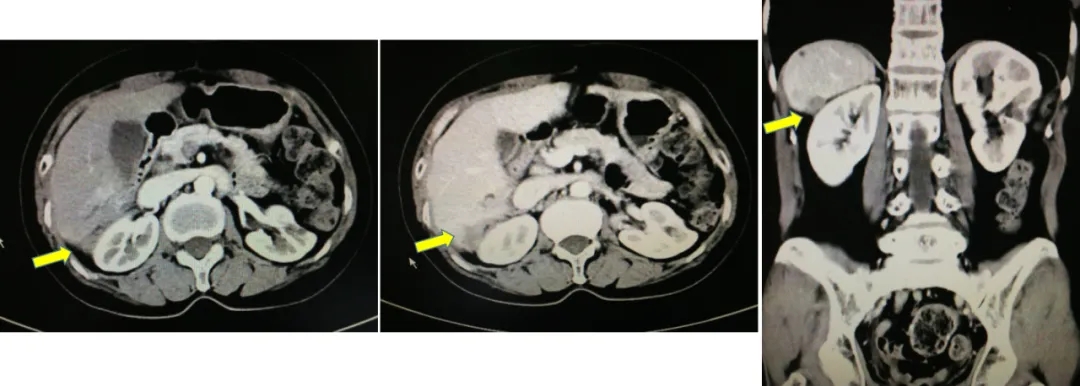

B超:肝脏右后叶近肾区局部片状回声欠均,左侧肾上腺区囊实性团。

2014.6.11 CT:脾周囊性低密度灶2.4*2.7cm,较2014.2.26增大,腹主动脉旁肿大淋巴结,考虑“卵巢癌复发”。

CT检查结果